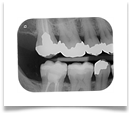

Nel nostro Studio impieghiamo un sistema radiografico computerizzato, il Vista Scan Plus della Dürr che consente di ottenere immagini di alta qualità (vedi confronto analogico/digitale) con dosi radiogene sensibilmente più basse per il paziente.

Con Vistascan Plus siamo in grado di ottenere, nel giro di pochi minuti, tutte le immagini che ci servono per un corretto ausilio diagnostico: bitewing, endorali, ortopantomografie, teleradiografie.